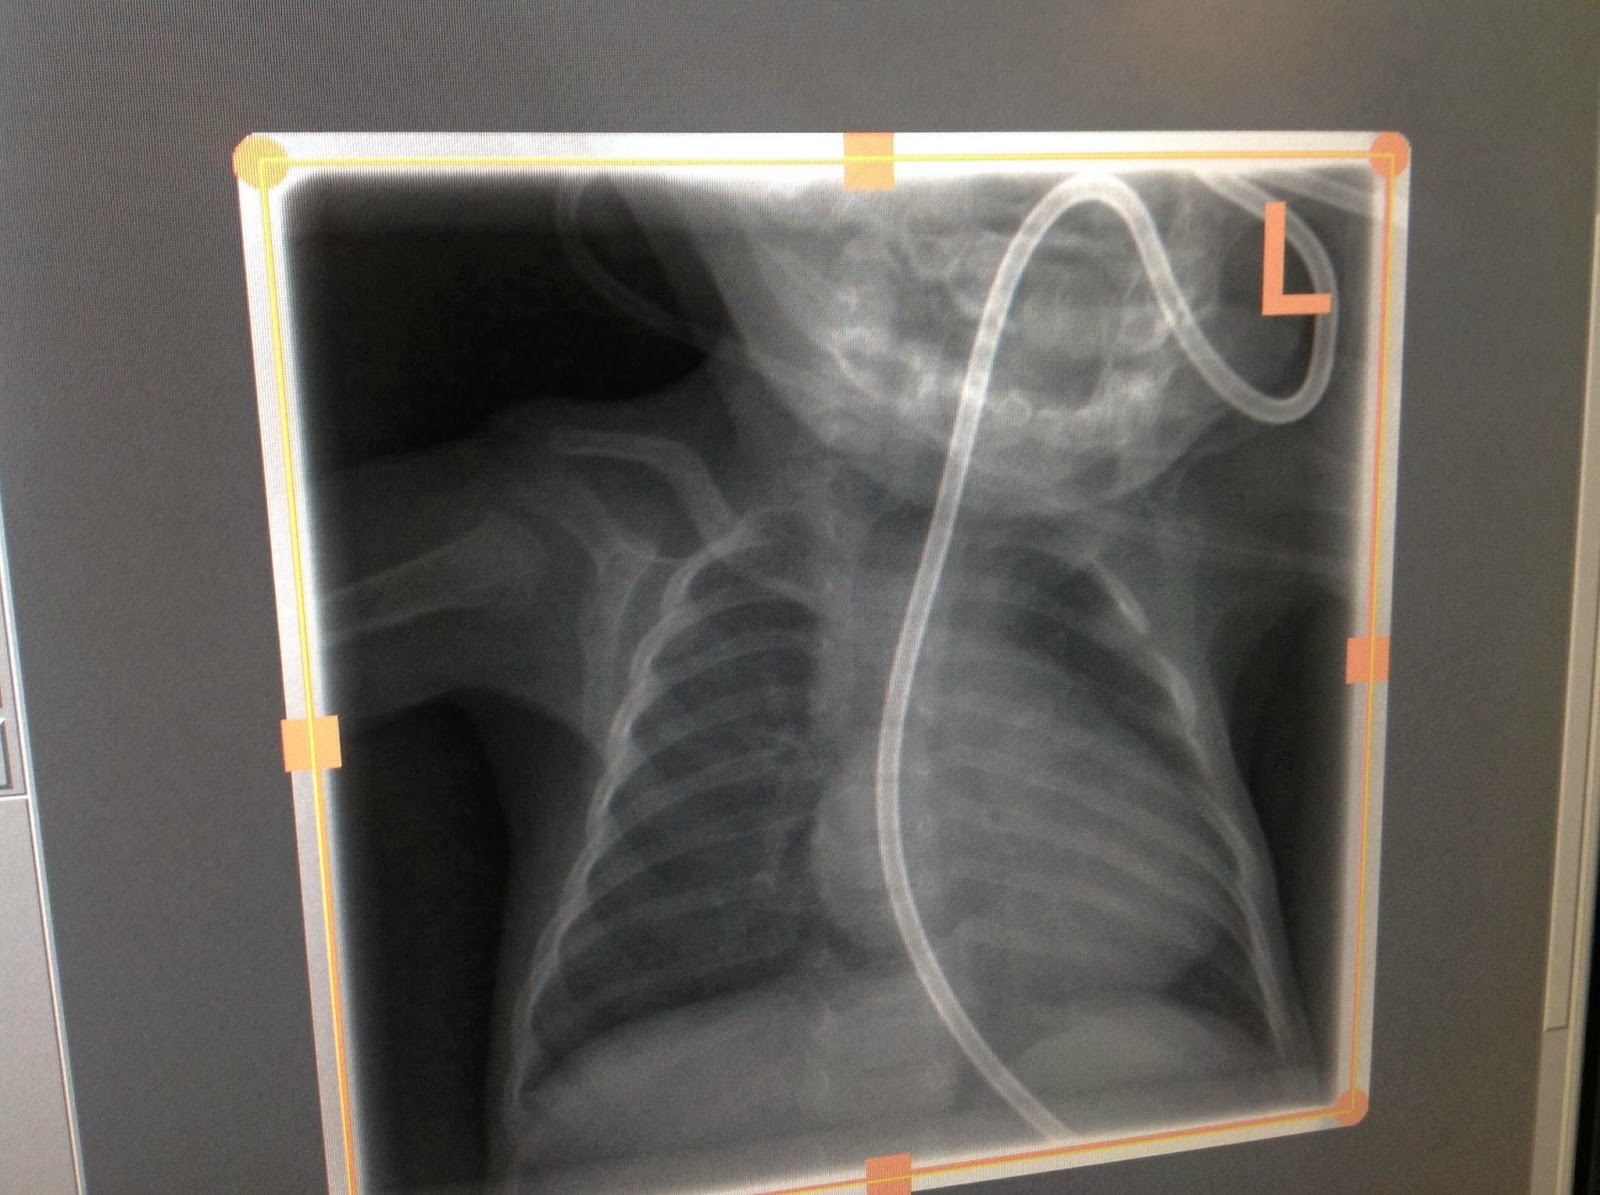

An NJ tube is just like the NG tube he had in the NICU (the one in his nose) but rather than going to his stomach it goes through his stomach and into his small intestine. The idea is that food gets put straight into his small intestine and isn’t thrown up because it isn’t in his stomach.

I was in the room, holding Noah’s hand while they did the upper GI to place the NJ tube. I watched on the x-ray screen as they got the tube to the appropriate location and started the barium injection to see how formula moved through his system. As it came out it was supposed to move forward but his looked like it hit a wall and backed up into his stomach, then started refluxing up his esophagus. That is where they found a narrowing in his small intestine that they believed could explain his vomiting. The food couldn’t get through!

![]() |

| Dec 23: X-Ray with an NJ tube |